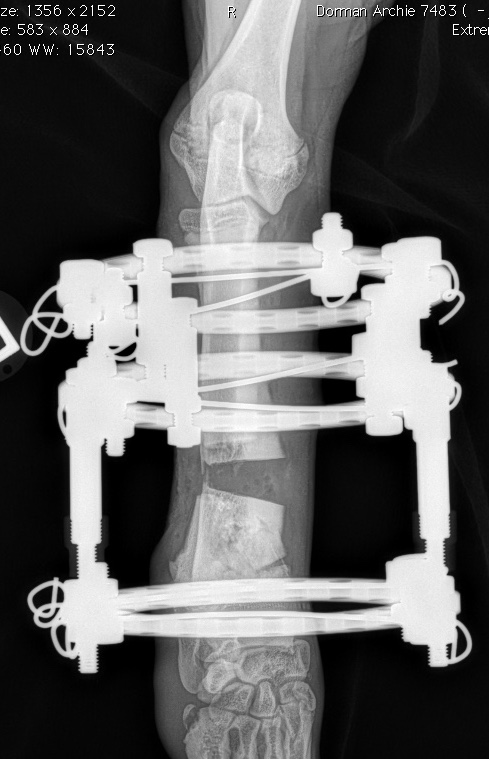

This image demonstrates the use of circular ring external skeletal fixation for gradual and incremental correction of limb alignment and limb lengthening of the radius-ulna in a dog. This device uses linear "motors" to distract and move the bones daily by use of a simple wrench. Limb lengthening may be achieved at a rate of approximately 1 mm per day.